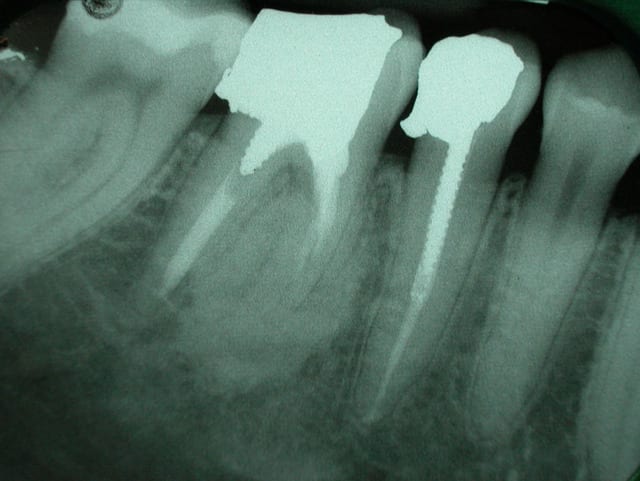

qu'est que cela peut il etre?

dent asymptomatique.

Normal mon chou, rien à faire lésion cemento-osseuse très difficile à classer même pour l'oms

tu peux écarter les fibromes cemento-ossifiant (il manque le halo radio clair périphérique) e n'est pas non plus une dysplasie fibreuse il n'y apas de déplacement de structure dentaire tu peux t'orienter vers une dysplasie céménto-osseuse péri apicale à forme dense quel age? Femme?

c'est^pas méchant, c'est souvent une formation cementoïde corrélable au traitement endo, l'os est fou et ne reconnaît plus les cellules cimentaire...

je ne suis pas endo, mais en temps qu'osseuphile je ne rettt pas pas d'inflammation sup dans ce flou ossifiant et les images en distal de la 7 c'est là depuis longtemps ou c'est de l'amalgame tout frais, fais ta couronne en expliquant la présence de cette image ostéocondensante à la patiente , femme 3 décade correspond bien avec une dysplasie cemento-osseuse terme anapath qui veut dire on s’en fout il ya des cellules cementaire et osseuses en structure malformative résultant d'une anomalie du développement d'un tissu .